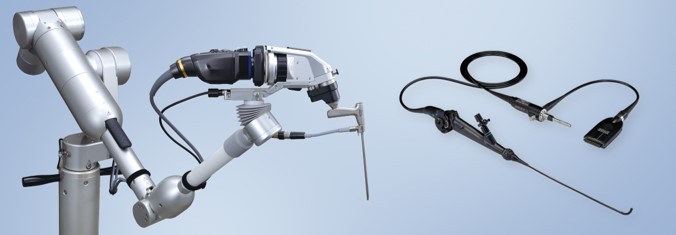

神経内視鏡手術とは?

神経内視鏡手術は、脳の中に直径3〜5mmの細い内視鏡を入れて脳の中の病巣を直接観察しながら行う手術のことです。手術時間は開頭手術に比べ半分程度と短く、患者さんの体への負担が少ない低侵襲な手術の一つとなります。

神経内視鏡手術の実際

これまでの手術用顕微鏡を用いた開頭手術では、どうしても病巣に対して視野が遠くなりますが、神経内視鏡では、より病巣に近接して観察できるため顕微鏡の死角を補ったりしながら治療することが可能です。また近接して横からや裏側からも観察することも可能で、正面からだけの観察より詳細な観察が可能となります。